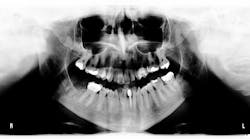

During a routine hygiene appointment, a 72-year-old man reported a "growth" on the roof of his mouth behind his upper left molar. He noted its presence for about two weeks with occasional bleeding. An oral examination revealed a solitary, reddish nodule measuring 7 mm in diameter in the gingival mucosa between teeth nos. 14 and 15.

The lesion was soft, tender to the touch, asymptomatic, and bled slightly when examined. Additionally, a defective crown on tooth no. 14 was observed. The patient indicated that the only recent change in his oral hygiene routine was using a different size of interdental brush in that area.